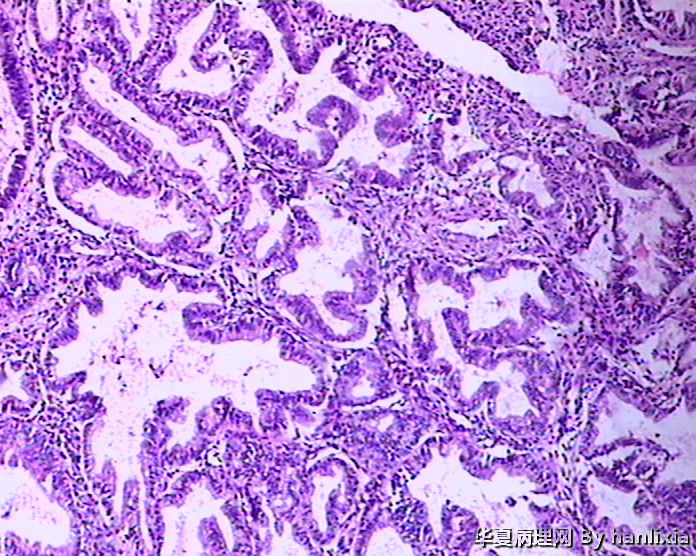

• 子宫内膜图1

图1

标签:45岁女性 闭经1年 阴道出血10余天 行诊刮术。

复杂性伴非典型增生

腺体密集,背靠背及共壁现象,腺体有成角,腺上皮增生呈多层,有内折,腺体与间质比例大于1:1.

子宫内膜复杂性增生伴中-重度不典型增生,图1-2可疑癌变